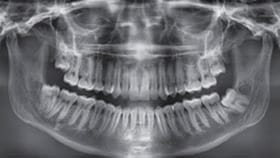

Guided implant surgery is a breakthrough technology which offers benefits previously unknown in implant dentistry. Guided implant surgery is a procedure in which precision surgical instrumentation is used in conjunction with three-dimensional CT images. Dedicated computer software, which allows visualization and manipulation of the images of the patient’s jaw bone and surrounding tissue, makes it possible for the most accurate approach to implant surgery. Traditional surgical guides are difficult to use predictably when there are no apparent anatomic references.

At Terrace Oaks Dental, we used Vatech Green CT in conjunction with our digital impression to create a perfect plan for our implant surgery cases.